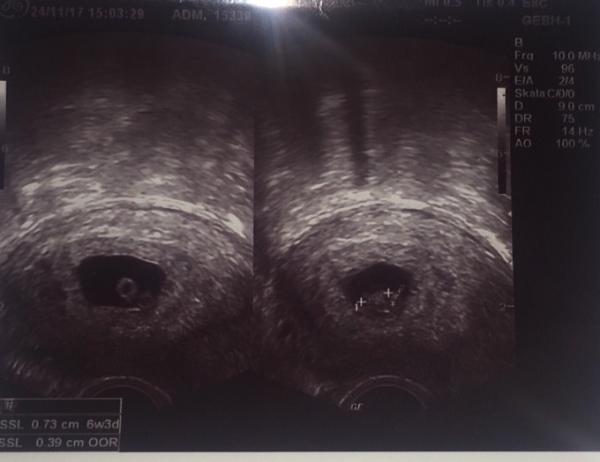

Hey Leute, ich hatte gestern bei 7+1 (jetzt zurückgestuft auf 6+3) meinen FA-Termin und dann die große Überraschung... 2 Embryos in einer Fruchthöhle Naja jetzt bin ich jedenfalls etwas verunsichert, da einer der beiden etwas kleiner ist... Hat jemand von euch schon Erfahrung mit so etwas? Meine Schwangerschaft war eigentlich nicht geplant, aber wir freuen uns jetzt natürlich trotzdem total! Ich würde nur gerne wissen was ich jetzt beachten muss, da es ja nun sogar 2 Würmchen sind... P.s. Auf dem Bild seht ihr 2 mal die selbe Fruchthöle, nur dass man in der links die Dottersäcke erkennt und in der rechts die beiden Würmchen Liebe Grüße!!

Bild zu Eineiige Zwillinge... - Schwanger - wer noch? Rund um die Schwangerschaft